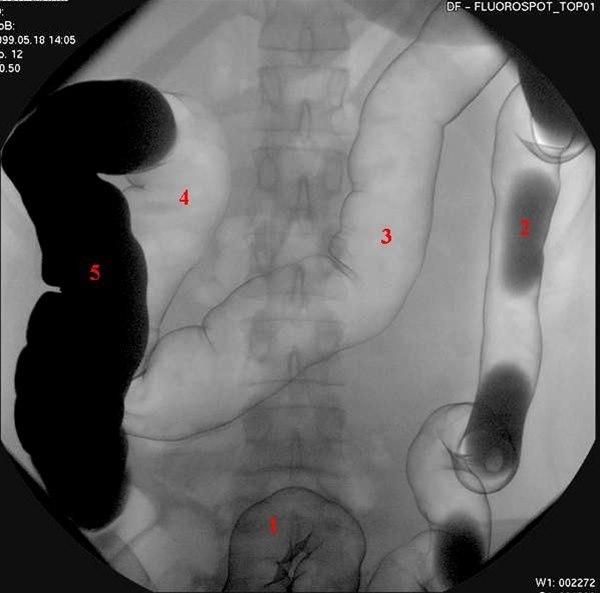

Colon dobbelkontrast

Dobbelkontrast teknikk med barium og luft

1. Sigmoideum

2. Descendens

3. Transversum

4. Høyre flexur

5. Ascendens